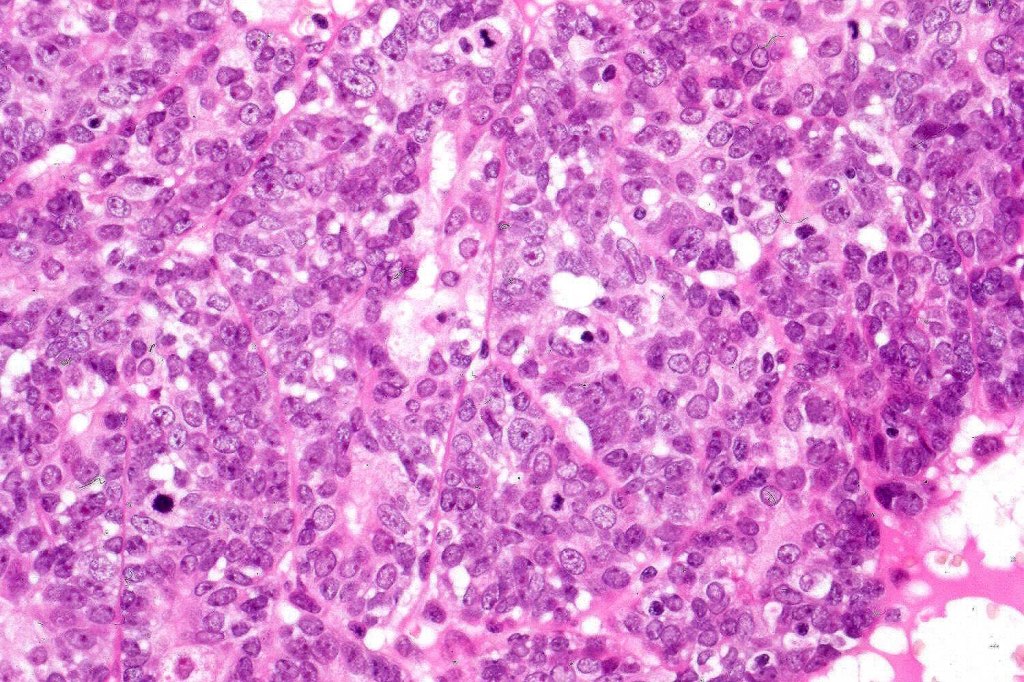

Histological features

•Pre-existent spiradenoma

•Malignant component shows loss of dual cell population, increased mitotic activity, atypical mitoses & necrosis

•The alternative classification into low grade (with only mild atypia and increased mitotic activity) and high grade variants has some merit although in any individual case this can be hard to apply unless the whole tumor has been sampled and is of uncertain biological merit.